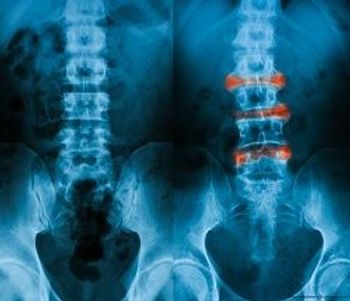

Be aware that changes in geometry, bone mineral density, and micro-structure appear early in the disease course of axSpA.